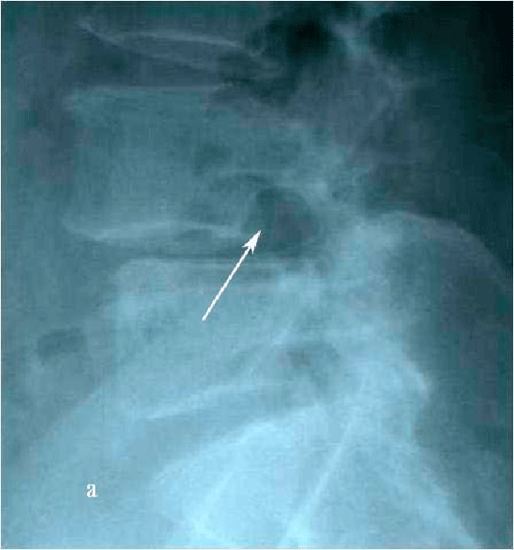

При контрольной рентгенограмме отмечено правильное положение транспедикулярной системы на уровне L4-L5 позвонков. (Рис.9a,b).

Рис. 9 a. Ренгенограмма поясничного отдела позвоночника в боковой (a) и прямой (b) проекции. Транспедикулярная фиксация  L4-L5 позвонков титановой конструкцией, удалена дужка L4 позвонка. Рис. 9 b. Ренгенограмма поясничного отдела позвоночника в боковой (a) и прямой (b) проекции. Транспедикулярная фиксация  L4-L5 позвонков титановой конструкцией, удалена дужка L4 позвонка.

Рис. 9 a,b. Ренгенограмма поясничного отдела позвоночника в боковой (a) и прямой (b) проекции. Транспедикулярная фиксация

L4-L5 позвонков титановой конструкцией, удалена дужка L4 позвонка.